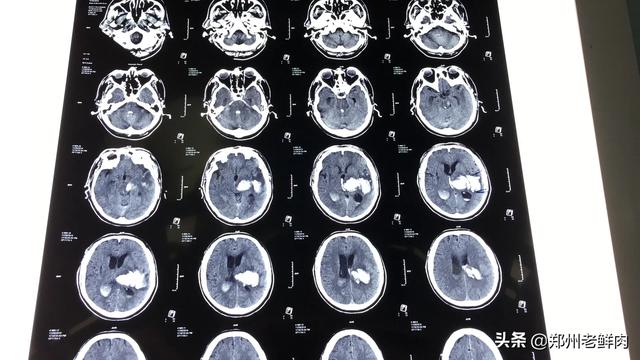

7日間で12回もCTを撮り、そのたびに家族に付き添ってもらったのに、なぜ医師はこんなことをしたのか?

いわゆるボトルがいっぱいになっていない、半分ボトルを振って、半端な知識の人々は常にインサイダーの容量でいくつかの非常に専門的な問題を質問するのが大好き、私は脳出血や脳損傷の患者を処理し、時には1日3〜4回ctは、我々はベッドサイドのctを持っていることを除いて、家族が同行する必要はありませんが、検査が必要である、トラブルは、次の時間は、まず本に行くために質問をすることですか?

医師の過剰検査が疑われ、CTは放射性物質が多く健康を害するとも言われている。家族の付き添いについては、重症の場合、いつでもサインなどが必要なため、家族の付き添いを認めるのであれば理解できるが、一般病棟に移っても家族や介護者の付き添いが必要というのであれば、本来、患者の観察や介護は病院の仕事であるはずなのに、病院が看護サービスを放棄しているとしか思えない。また、患者の家族が病院という環境に長期滞在することで、例えば呼吸器系の入院病棟で空気感染するなどの健康上の問題は生じないのだろうか。病院が患者の介護の仕事(しかも患者負担のプログラムである)を患者の家族の肩に押し付けるのは、間違いなく職業倫理の問題である。それは、医師と患者の対立を激化させるだけである。

7日間、このCTを何十回も行うことは、通常の病院では不可能なことは、純粋なナンセンスです。病院に行って検査をすることは、明示的に規定されており、医療保険償還の問題にも関わるので、医療保険局も監督と検査を実施する。医師は無謀なことはしない。通常のCT検査は、必要な場合を除き、1ヶ月以上の間隔を置くのが一般的で、その間隔が長いのは、病状の比較判断や治療効果の有無を確認するためであり、無差別にCT検査をして儲けることはできず、そこの医療保険局もパスすることはできない。正直なところ、病院はあなたからお金を儲けたいのです。あなたが気づかないだけで、このような誰もが知っている愚かな方法を使用することは不可能です。